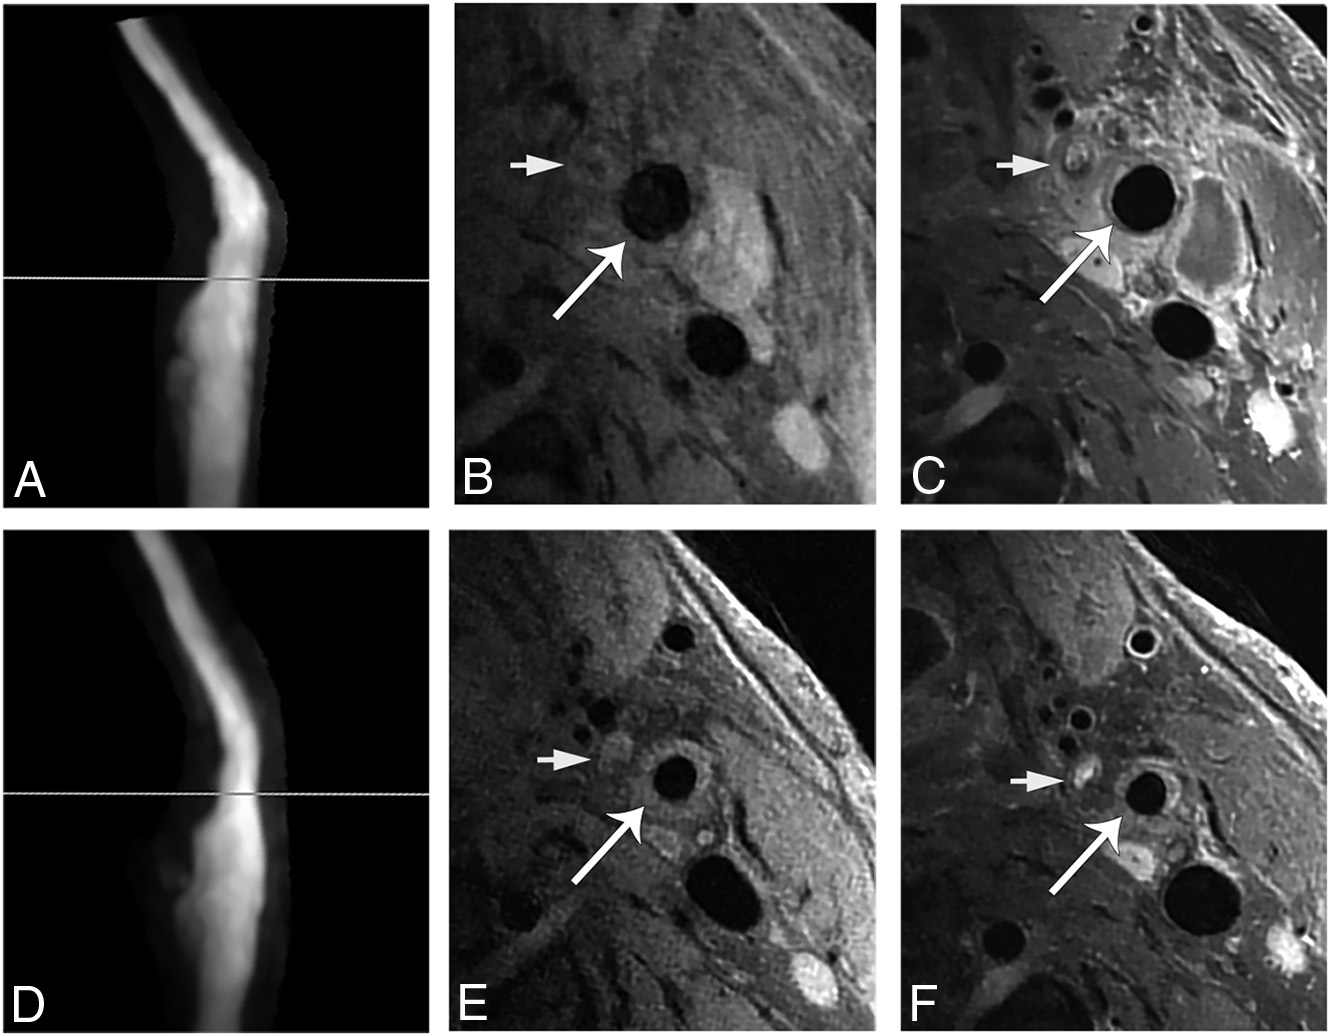

图1 从CEA后正常形态发展到MH。CEA手术后2个月,TOF-MRA(A)显示预期的血管形态。ICA近端同一部位(A中的直线)的增强前(B)和增强后(C)血管壁MRI(vessel wall MR imaging,VWMRI)显示血管壁增强,但ICA近端没有血管壁异常增厚(长箭头)。CEA10个月后TOF-MRA(D)显示管腔狭窄。在相同部位(D中的直线)的增强前(E)和增强后(F)VWMRIs显示血管壁环形增厚,伴有轻度不均匀强化,符合MH的特征(长箭头)。B,C,E和F中的短箭头表示颈外动脉